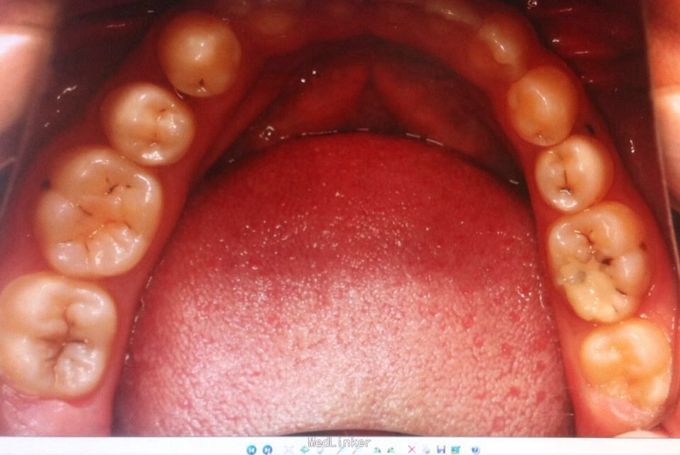

恒牙期 左右磨牙近中关系 12,22舌侧错位 32、33融合牙 右侧磨牙反合 上下牙列轻度拥挤 关节有弹响

治疗中可能需片磨上牙(下颌融合牙引起bolton指数不调)